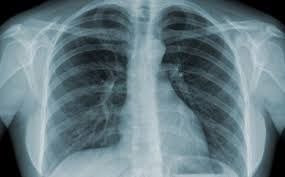

Lao phổi trên chẩn đoán hình ảnh

Chẩn đoán hình ảnh dùng trong chẩn đoán lao phổi thường là X quang phổi và CT phổi có thể có tiêm thuốc cản quang, không tiêm thuốc cản quang hoặc chụp độ phân giải cao. Cùng tìm hiểu rõ hơn về bệnh với bài viết ngay dưới đây nhé!

Bệnh lao là một bệnh truyền nhiễm thường ảnh hưởng đến phổi. Nó là kẻ giết người lớn nhất thứ hai do một tác nhân lây nhiễm đơn trên toàn thế giới, và trong năm 2012, 1,3 triệu người chết vì căn bệnh này, với 8,6 triệu người ngã bệnh.

Lao thường ảnh hưởng đến phổi, mặc dù nó có thể lây lan đến các bộ phận khác trên cơ thể.